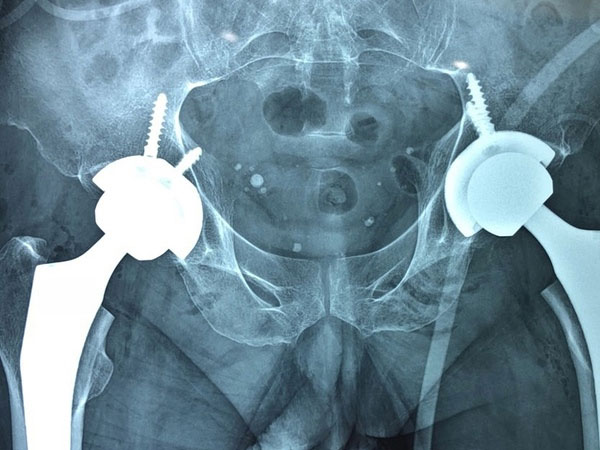

08/03/2021 23:09Trông cháu, người đàn ông gãy 2 bên khớp háng sau cú ngã nhẹ

Mới đây, khi đang trông cháu ngoại, ông bị ngã phệt xuống sàn và lập tức bị mất vận động 2 chân. Ông đến Bệnh viện Hữu nghị Việt Đức với biểu hiện gãy cổ xương đùi 2 bên trên nền hoại tử vô khuẩn chỏm.

Bệnh nhân đã được các bác sĩ thay cùng lúc cả hai bên khớp háng, bởi nếu thay từng bên một, người bệnh phải chờ thêm 1-2 tuần, khi một bên phẫu thuật ổn định. Như vậy người bệnh vẫn đau đớn và phải chống chọi với những biến chứng do nằm lâu nên quyết định thay cả 2 khớp háng cùng lúc.

Việc thay khớp háng cùng lúc đòi hỏi mổ rất nhanh, gây mê hồi sức bảo đảm, trang thiết bị đầy đủ, theo dõi và hồi sức sau phẫu thuật chu đáo và cẩn thận mới an toàn cho người bệnh.

Sau phẫu thuật, bệnh nhân tiếp tục được theo dõi và điều trị tại Khoa Phẫu thuật Chi trên và Y học thể thao. Dự kiến sau một ngày phẫu thuật, bệnh nhân có thể ngồi dậy được. Sau hai ngày phẫu thuật, người bệnh có thể tập đi sớm với sự hỗ trợ của nạng/khung trợ đỡ.